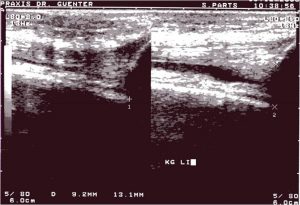

Abb.9 Sonogramm eines Kniegelenkes längs suprapatellar ohne (Bild li) und mit (Bild re) forcierter Streckung, so dass sich Erguß darstellt

Die Sonographie zeigt einen echoarmem Raum innerhalb eines Gelenkes (Abb.9 und 10) bzw. um eine Sehne (Spiegelei-Phänomen).